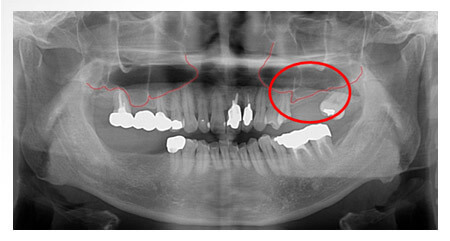

開窗提竇術